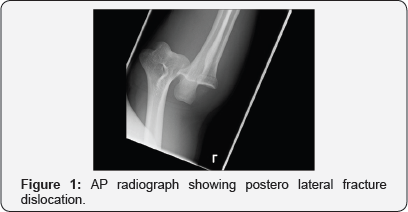

A 37 year old right hand dominant male sustained an injury when he came off a mountain bike at approximately 35 mph. His primary survey revealed no life threatening injuries but he had sustained bilateral closed upper limb injuries. On the left side he sustained a terrible triad injury of the elbow -i.e. a fracture dislocation of the ulnohumeral joint with an associated coronoid and radial head fracture (Figures 1 & 2). In addition he sustained an injury to the right distal radius which showed a dye-punch type intra-articular fracture. He was neurovascular intact throughout.